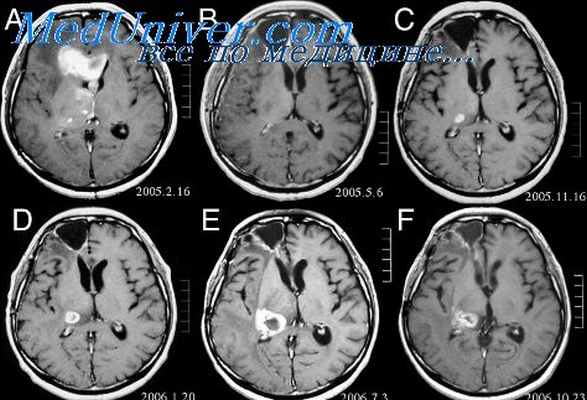

- (МРТ) — основной метод визуализации, обычно используемый для оценки астроцитомы. Изображения, сделанные с помощью МРТ, могут дать больше информации о типе опухоли и потенциальном развитии заболевания. Кроме того, МРТ проводится после хирургической операции, чтобы удостовериться, что опухоль полностью удалена. (КТ) позволяет создавать изображения поперечного сечения органов и тканей внутри тела с помощью рентгеновских лучей. Специальный аппарат сделает множество снимков, чтобы составить детальное изображение. Это позволяет обнаружить опухоли очень маленького размера.

Маркированная астроцитома на МРТ в осевой проекции

МРТ во фронтальной плоскости с метками размеров астроцитомы

МРТ астроцитомы в сагиттальной плоскости